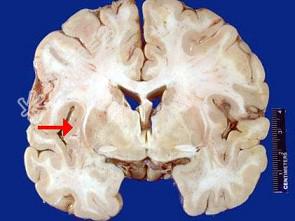

- 单项选择题如图箭头所示为大脑哪个部位 ( )

A、壳核

B、颞叶

C、尾状核

D、岛叶

E、海马